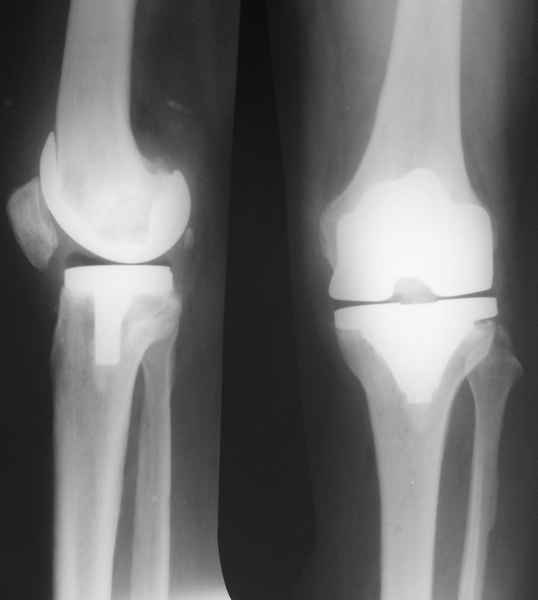

13/02/07 |  25/07/07 |  дек. 07 |  25/06/08 |  14/01/09 | Через 1 месяц после операции объем движений 90 градусов, через 2 месяца 60, через 3 - 40, через 5 - качательные движения.

В июле 2007 года выполнена ревизия - полости сустава нет. Капсула сустава имеет толщину от 1 до 1.5 см, собственная связка надколенника имеет толщину до 3 см. Сустав заполнен фиброзно-рубцовой тканью. Компоненты стабильны.

Есть вопросы к установке протеза. Скорее всего тибиальное плато было не конца резецировано и в задненаружных отделах осталась ступенька. Это привело к тому, что тибиальный компонент завалился на варус.

Ты мне говорил об этом случае, а теперь я увидел снимки. Для исключения или подтверждения гнойного процесса надо взять обязательно посев. По-моему и бедро шатается. Ревизовать при ислючении гнойно-септических осложнений надо полностью либо CCK комплектом или связанным.